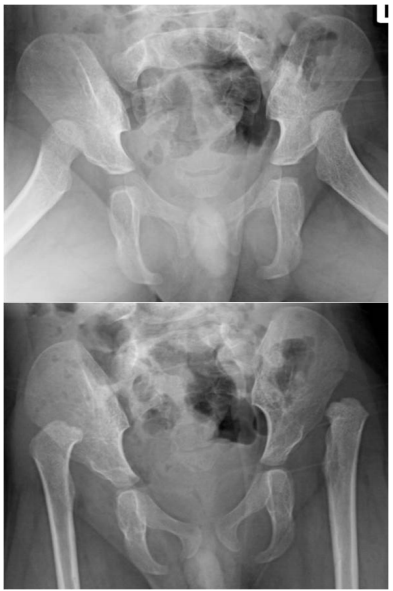

72 一位 3 歲小朋友,因走路不穩就診,骨盆及髖關節 X 光攝影如下圖,最可能之診斷為何?

(A)Legg-Calvé-Perthes disease (B)slipped capital femoral epiphysis (C)congenital dislocation of hip (D)osteochondroses